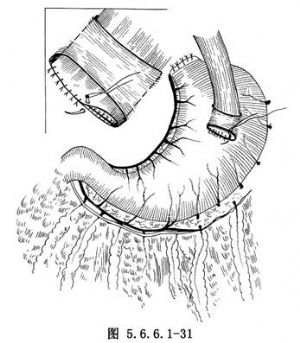

(4)吻合口后壁缝完后,将胃管及十二指肠饲食管的引导糖球置入胃中。吻合口前壁为食管壁全层与胃壁上第二个横切口下唇的胃壁全层,用细丝线间断缝合,缝线结可以打在腔外。注意由后壁转向前壁的转角处缝线必须准确,所有缝线打结切记不能太紧(图5.6.6.1-31)。